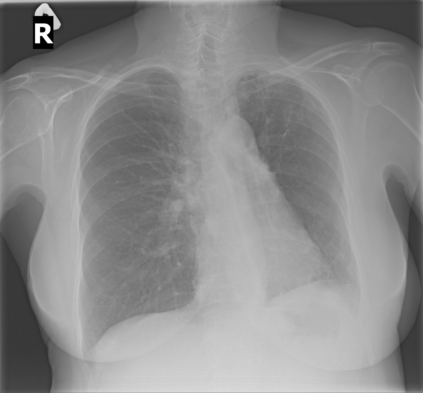

The evaluation of infectious disease processes on radiologic images is an important and challenging task in medical image analysis. Pulmonary infections can often be best imaged and evaluated through computed tomography (CT) scans, which are often not available in low-resource environments and difficult to obtain for critically ill patients. On the other hand, X-ray, a different type of imaging procedure, is inexpensive, often available at the bedside and more widely available, but offers a simpler, two dimensional image. We show that by relying on a model that learns to generate CT images from X-rays synthetically, we can improve the automatic disease classification accuracy and provide clinicians with a different look at the pulmonary disease process. Specifically, we investigate Tuberculosis (TB), a deadly bacterial infectious disease that predominantly affects the lungs, but also other organ systems. We show that relying on synthetically generated CT improves TB identification by 7.50% and distinguishes TB properties up to 12.16% better than the X-ray baseline.